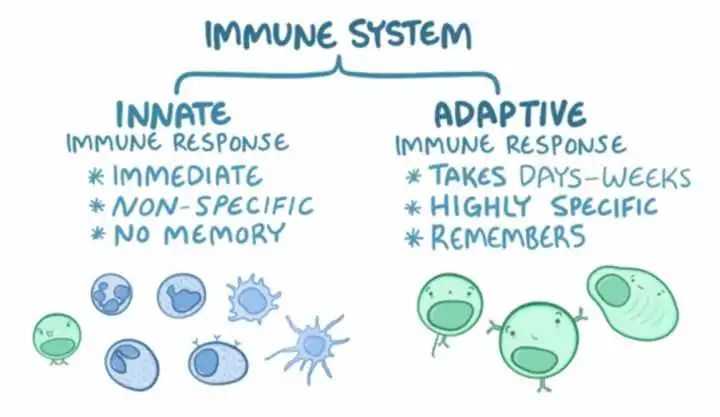

而熬夜除了对我们的心脑血管系统以及神经系统造成损伤以外,还会对免疫系统造成进一步的损害。多项研究表明,睡眠和免疫系统是密切和双向相关的。睡眠剥夺与先天性和适应性免疫系统的变化有关,睡眠不足会导致免疫细胞数量和功能下降,从而使身体更容易受到感染。

对于有害的病毒、细菌和化学物质,我们的免疫系统会首先启动「先天免疫反应」,通过发烧、流涕、呕吐、腹泻等各种方式,杀灭并排出致病物质。这种大规模的杀伤虽然速度快,但对于未知的病原体就没有效果。这时候,我们的身体会启动「获得性免疫反应」,针对敌人的特点研发特效武器,虽然这个过程会花费几周的时间,但一旦研发成功,就会形成“免疫记忆”。

左边:先天免疫大家族;右边:后天免疫大家族